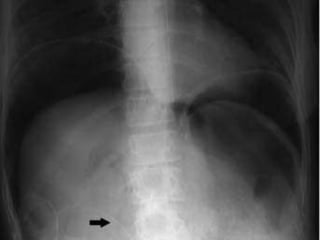

IMÁGENES CLASICAS DIAGNOSTICAS EN

EL 20%

Pruebas diagnosticas • Ecografía •Tomografía axial computarizada • Resonancia magnética nuclear • Lavado peritoneal diagnóstico • Laparoscopia • Radiografía de tórax • Placas simples de abdomen

IMÁGENES CLASICAS DIAGNOSTICASEN EL 20% SENSIBILIDAD 10%